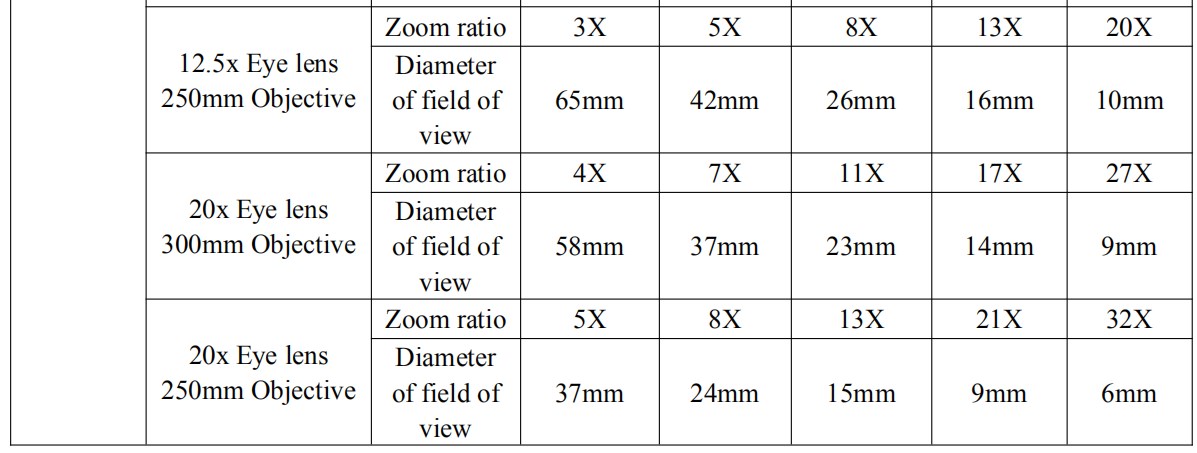

Binocular eyepiece technical parameter